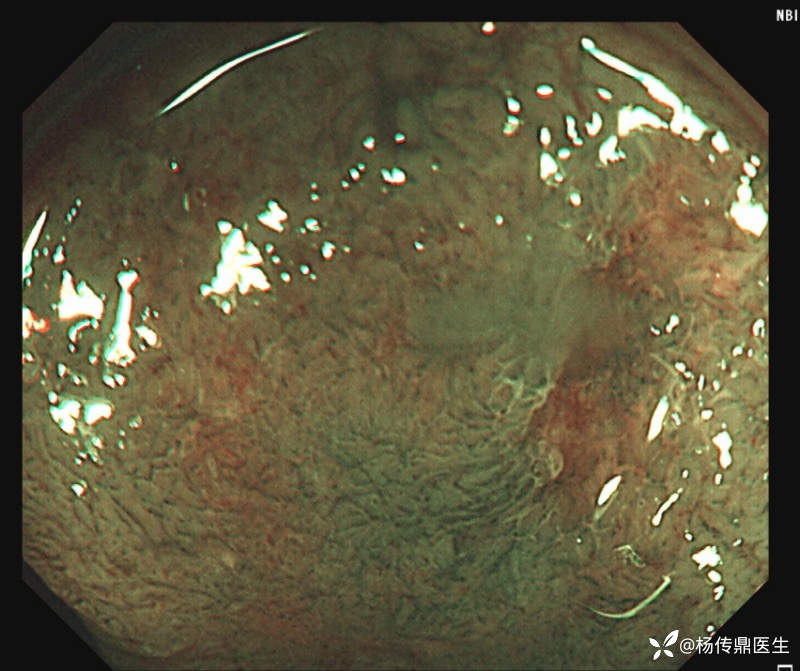

患者男性,57岁,体检行肠镜检查,大肠多发性息肉,直肠侧向发育型息肉。内镜下考虑癌变了,但是病理报了高级别,是ESD还是外科?该怎么跟患者沟通?